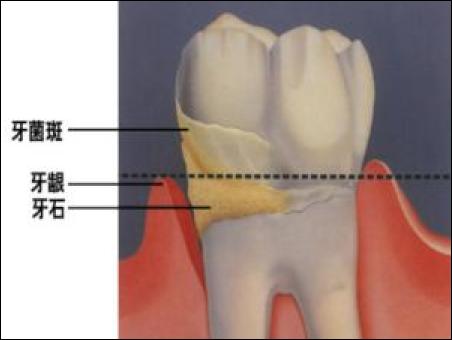

牙結(jié)石是如何附著在牙齦周圍的